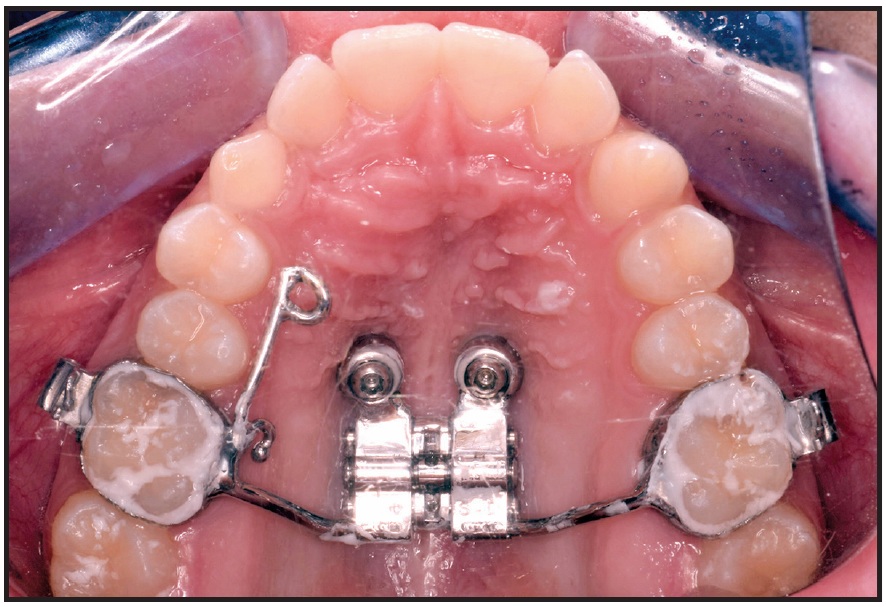

After local anesthesia (2% lidocaine) was administered in the surgical sites, the surgical guide was fitted to the occlusal surfaces of the posterior teeth. Two OrthoEasy Pal** miniscrews were inserted into the adapted pickup driver and mounted on a contra-angle handpiece at a low speed of 40rpm (Fig. 8). The cylindrical guide tubes were designed according to the dimensions of the pickup driver to ensure that the screws were inserted at the correct angle and the planned depth (Fig. 9).

Fig. 9 Two parallel miniscrews after insertion in anterior palate.

After impression transfer copings were placed over the miniscrew heads, a precision impression was taken with vinyl polysiloxane, and the miniscrew positions were replicated with two analogs (Fig. 10). A hybrid Hyrax‡‡ expander was fabricated with an anterior arm on the right side and an attached eyelet that would serve as an occlusal guide for traction of the impacted canine (Fig. 11). The arm was designed to generate a force vector capable of moving the canine crown distally and occlusally, thus facilitating guided eruption.